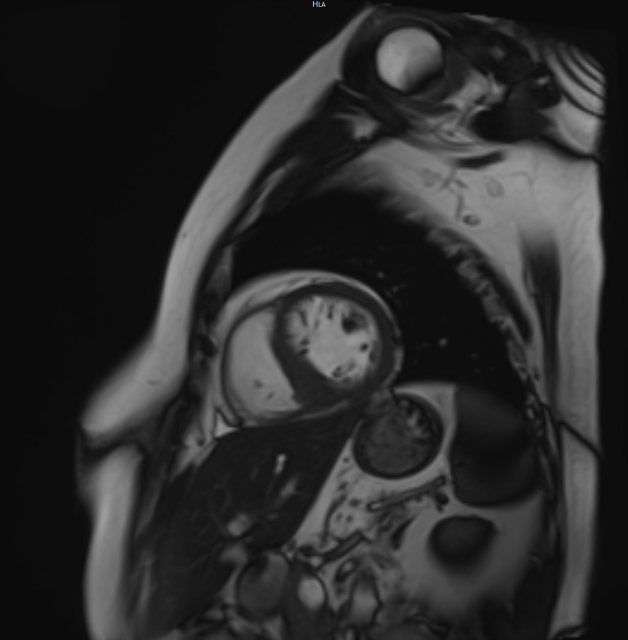

技术名称:心脏磁共振成像(Cardiovascular Magnetic Resonance, CMR),简称心脏核磁

心脏核磁是目前心血管疾病诊断领域无创、无辐射、精准度极高的核心影像学技术,依托磁共振多序列、多参数成像原理,可清晰呈现心脏的解剖结构、心肌形态、心功能状态、心肌血流灌注及心肌活性等关键信息,被业界誉为评估心脏结构与功能的“金标准”。

该检查无需穿刺、无电离辐射,安全性高,能为临床提供全面、定量的心脏评估数据,为心血管疾病的早期诊断、精准分型、疗效评估及预后判断提供可靠依据,是现代心血管诊疗的重要技术支撑。